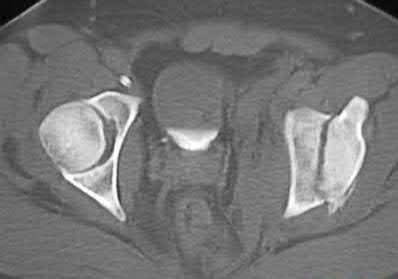

Which of the following images shows an injury pattern most consistent with a lateral compression type 3 pelvic ring injury?

Figure C is an axial CT scan of a lateral compression type 3 (LC3) pelvic ring injury.

Classically, LC3 injuries demonstrate an ipsilateral lateral compression and a contralateral APC (windswept pelvis) fracture pattern. The most common mechanism of injury in these cases is a rollover MVC or pedestrian vs. auto. LC1 injuries are characterized by an oblique or transverse ramus fracture and ipsilateral anterior sacral ala compression fracture, while LC2 injuries consist of a rami fracture and ipsilateral posterior ilium fracture dislocation (crescent fracture). While LC1 injuries can often initially be managed conservatively with protected weight-bearing and close observation, LC2 and LC3 pelvic ring injuries are almost universally operative.

Pennal et al. discuss a radiologic technique for assessing the forces producing pelvic disruption and its use in logically classifying pelvic injury. Based on this radiologic assessment and along with some biomechanical studies, they propose a classification system involving three major forces producing injury that can also be helpful in the management of these patients.

Young et al. performed a retrospective analysis of the plain radiographs of 142 cases of pelvic fractures and identified four patterns of force that presented with distinctive, recognizable radiographic appearances. They describe a classification system for pelvic fractures based on radiographic and clinical findings that correlates with associated injury to soft-tissue structures and enables the surgeon to begin corrective procedures rapidly.

Incorrect Answers:

Answer 1: This represents a lateral compression type 2 injury. Answer 2: This represents a lateral compression type 1 injury.

Answer 4: This represents an anterior posterior compression type 2 injury. Answer 5: This represents an anterior posterior compression type 3 injury.